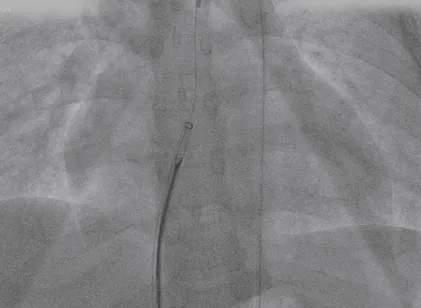

术前造影

主动脉瓣上造影,破口约5mm

轨道建立

导丝通过主动脉窦瘤破口

导丝置于下腔静脉

圈套器抓取导丝建立完整轨道